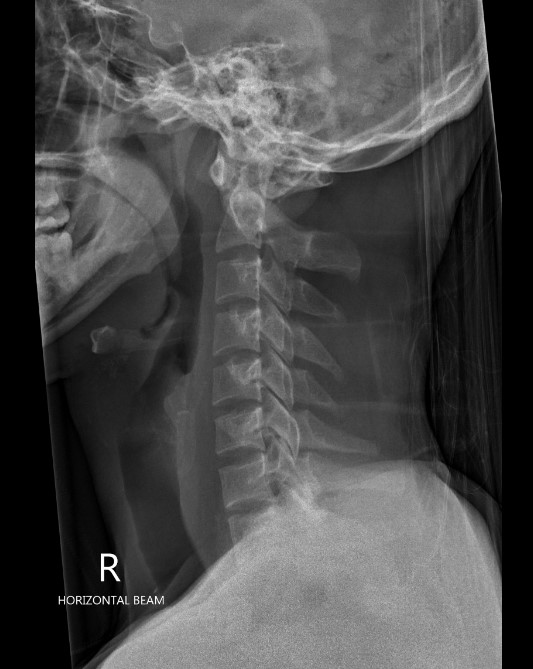

Increased ADIADI

Lateral radiographs demonstrating increased ADI